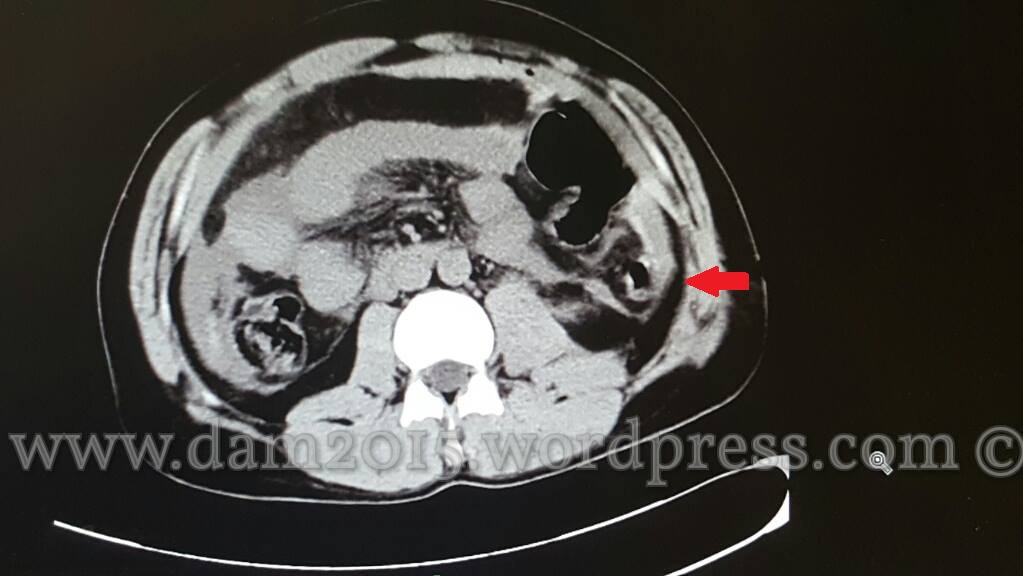

Paziente uomo, 35 anni, con ferita penetrante da arma bianca in fianco sinistro.

Addome acuto, emoperitoneo, aria libera endoperitoneale.

Ferita da punta e taglio di ansa digiunale.

Presenza di aria libera endoaddominale.

Quota di versamento periepatico.